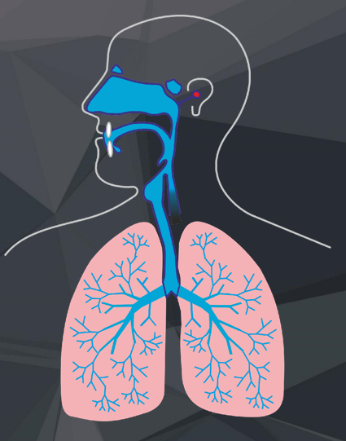

Bei jedem aktiven Druckausgleich wird „Luft“ durch Hohlräume in das Mittelohr bewegt.

Luftgefüllte Hohlräume:

- Lunge

- Mundhöhle

- Nasen-Rachenraum

- Mittelohr